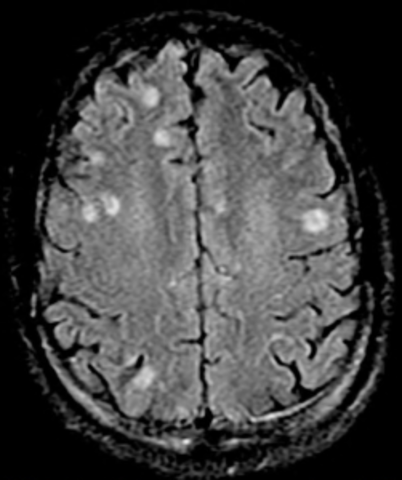

Death Peak:Toxoplasmosis gondii reached its severe and potentially fatal disease peak of adults in 1968 after several cases of toxoplasma encephalitis were found in patients with cancers.

Toxoplasmosis gondii: Widely Recorded:Toxoplasmosis gondii became excessively recorded as a cause of morbidity in immunodeficient patients, including AIDS patients beginning in 1983.

Present:T. gondii continues to be an important disease in the modern world, especially in pregnant women and immunocompromised patients.